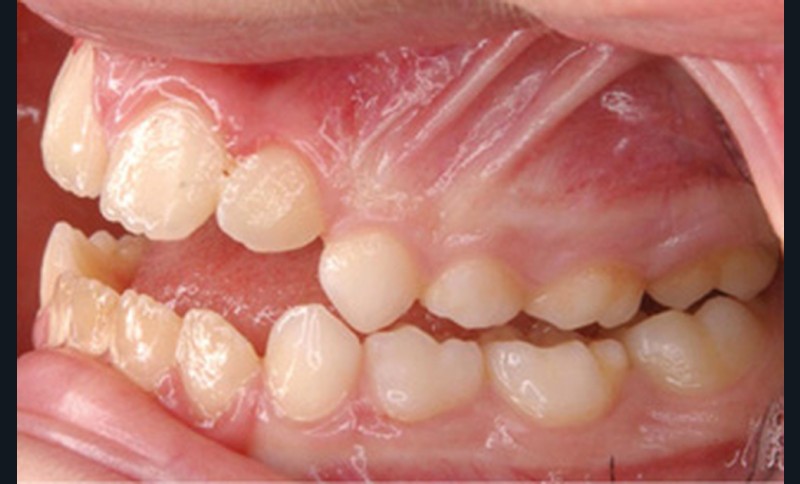

Cette patiente a été suivie dans le cadre d’un traitement interceptif alors qu’elle avait 9 ans. Elle présentait une endognathie maxillaire et une béance antérieure importante liées à des troubles fonctionnels évidents. En effet, l’examen clinique révélait une ventilation buccale exclusive, des ronflements nocturnes et une déglutition atypique. Nous avions noté à l’époque un manque de place pour l’évolution des dents définitives et un inversé d’articulé bilatéral. Les parents avaient rencontré un médecin ORL, mais avaient refusé une intervention visant à enlever les amygdales. Les deux canines maxillaires étaient incluses (fig. 1 à 6).

Quelques années plus tard, au moment de démarrer sa prise en charge orthodontique, la patiente présentait à nouveau une béance antérieure, un décalage des milieux incisifs de 2 mm et le problème transversal avait récidivé. Lors de l’examen clinique, elle présentait un inversé d’occlusion bilatéral postérieur et une ventilation buccale exclusive. À la suite du refus de réaliser l’amygdalectomie de façon précoce, elle ronflait toujours et sa déglutition ne s’était pas modifiée malgré des séances d’orthophonie (fig. 7 à 15).